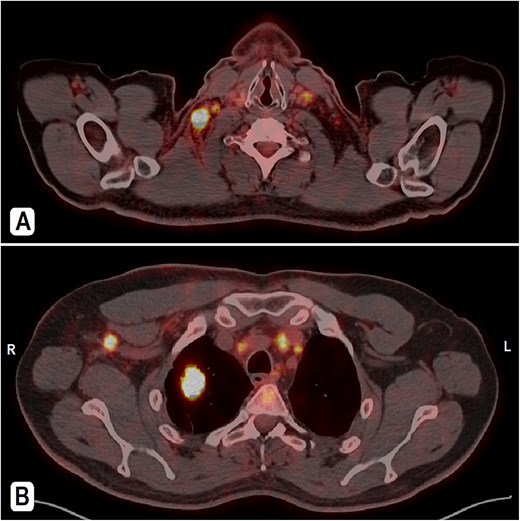

A 56-year-old male patient, married with four offspring, non-smoker, with free past medical and surgical history, presented to his family doctor complaining of a self-palpable, painless lump in the right submandibular area for 1-month duration. Family history included a brother with colon cancer. On examination, a right submandibular lump was noted, measuring ~2 cm, there is also a single painless, retro-areolar palpable breast lump with multiple right palpable lymph nodes. There were no skin or nipple changes. Neck ultrasound revealed right submandibular lymph node enlargement with bilateral prominent suspicious cervical lymph nodes. A CT scan showed a spiculated lesion in the right lung apex with adjacent atelectatic bands, pathologically enlarged hilar, mediastinal, and right-sided axillary lymph nodes. Additionally, there is noted asymmetry of breast tissue with right-sided retro-areolar soft tissue density (Fig. 1A and B). A positron emission tomography (PET) scan emphasized hypermetabolic, mildly prominent, multilevel cervical lymph nodes with intense fluorodeoxyglucose (FDG) uptake (SUVmax 13.3), extending to bilateral supra and right infraclavicular fossae, with the largest node in the right level 1 measuring 1.5 × 1.3 cm. A hypermetabolic right pulmonary apical soft tissue lesion was noted, measuring 2.9 × 2.4 cm with adjacent atelectatic bands, associated with hypermetabolic mediastinal and right axillary lymph nodes with intense FDG uptake (SUVmax 7.2) (Fig. 2A and B).

PET-CT scan. (A) At the neck level showing intensely hypermetabolic enlarged cervical lymph nodes. (B) An intensely hypermetabolic right upper lobe lung mass, with metastatic right axillary and mediastinal lymph nodes.